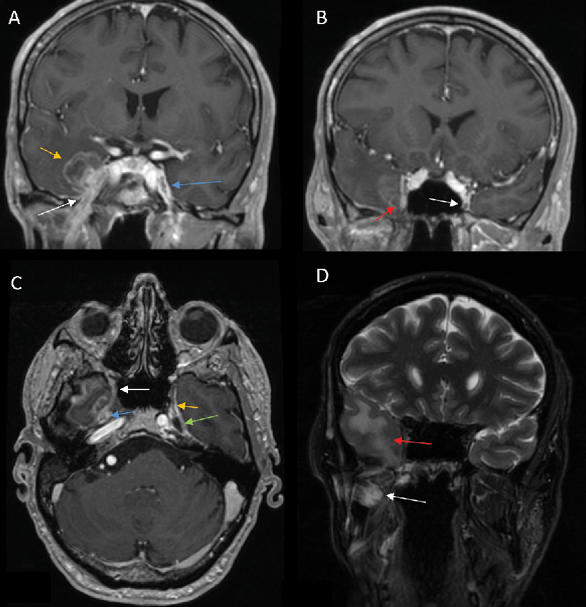

1) PNS commonly presents as enhancement of the affected nerve, which is attributed to the disruption of the blood-nerve barrier caused by the tumor growth and the associated nerve damage [28]. This enhancement is frequently accompanied by nerve enlargement due to multiple pathophysiological processes including tumor infiltration, inflammation, interstitial edema, and neurotrophic factor-induced hypertrophy [1]. However, in some instances, enhancement may occur without appreciable nerve enlargement, thus creating diagnostic challenges in radiological detection. Magnetic Resonance Imaging (MRI) optimally demonstrates both neural enhancement and enlargement, particularly when extending through neural foramina. Pathologic enhancement is characterized by diffuse, uninterrupted enhancement with no clear demarcation from the Perineural Vascular Plexus (PNVP) (Fig. 1, A, B and C) [2]. Careful evaluation of the enhancement intensity, thickness, and symmetry between the sides is essential to identify pathological changes. On CT, although individual nerves may not be well-defined, excessive contrast enhancement in neural foramina or canals can indicate nerve involvement [29].

4) On CT or MR imaging, replacement of the fluid signal in Meckel’s cave by a solid and enhancing lesion (Fig 1 C) indicates invasion of the trigeminal cistern [29].

In the acute phase (<1 month), MRI findings are characterized by T2 hyperintense edema-like signals, best visualized on fat-suppressed T2-weighted sequences (Fig. 1 D), and contrast enhancement of the affected muscles, which is most prominent on post-contrast, fat-suppressed T1-weighted images. An increased muscle volume is also noted [29]. During the first four weeks of denervation, there is a shift in water distribution, with a relative decrease in intracellular water and a corresponding increase in extracellular water, while the total tissue water remains unchanged. This redistribution leads to hyperintense signals on T2-weighted MR images, mimicking edema, as the T2 relaxation time of extracellular water is longer than that of intracellular water [31]. Additionally, enhanced contrast uptake is observed in the affected muscles due to increased perfusion and contrast medium accumulation in the extracellular space [31]. Notably, the denervated muscle retains its internal striation, distinguishing it from the muscle infiltrated by tumors, which disrupts the muscular architecture [2]. On PET imaging, there is typically increased 18F-FDG uptake in the affected musculature due to hypermetabolism associated with acute denervation [32].